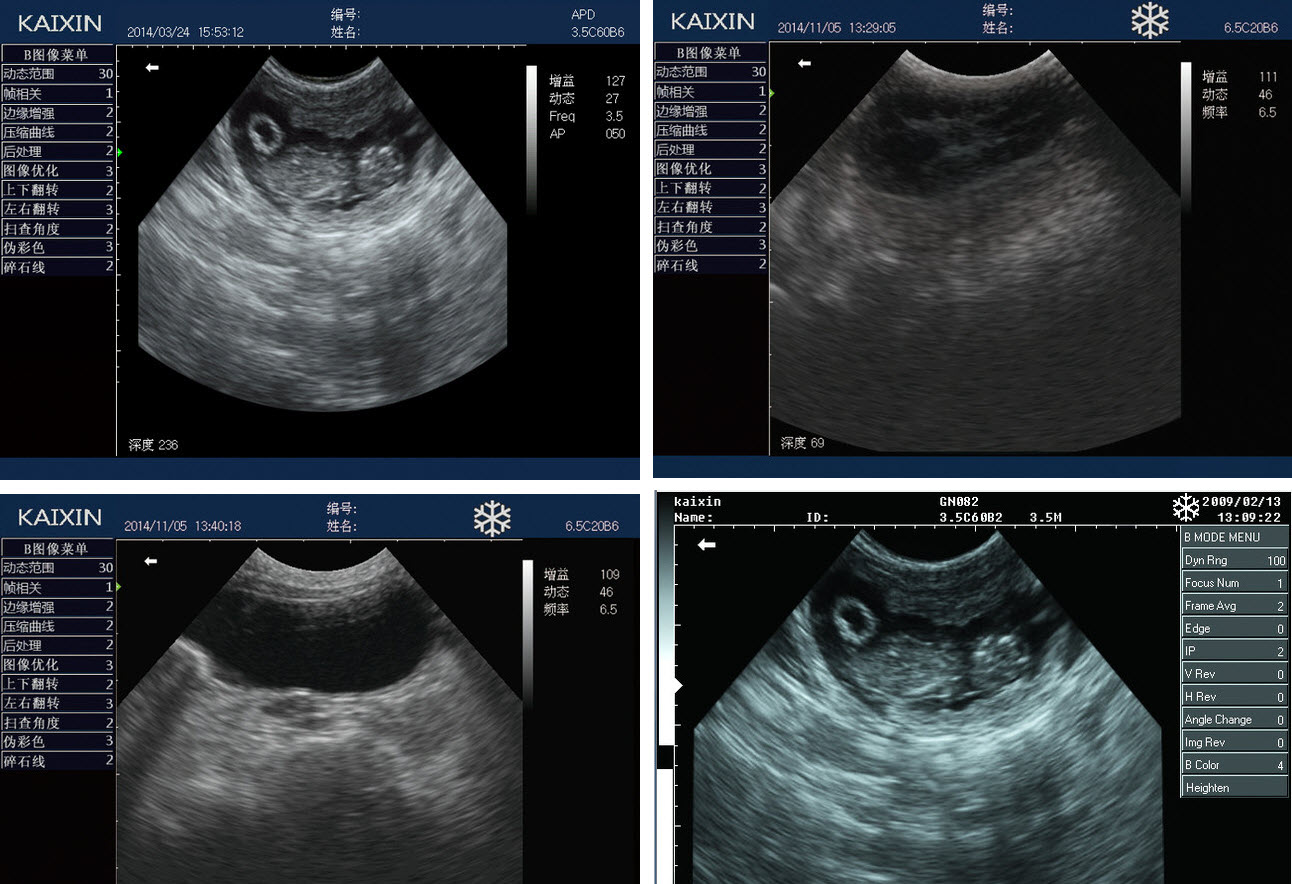

15.High quality clinical image

| 10.4’ high resolution color LED backlight display, with high contrast and wide viewing angle; | |

| Display mode | B、2B、4B 、B/M、M ; |

| Adjustable depth | 10 grades, max depth to 236mm; |